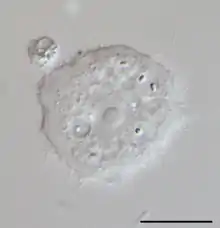

الشوكميبة هي جنس من الطلائعيات تتبع فصيلة الشوكميبات من رتبة الأميبيات الوسطية،[2] وتتواجد بكثرة في مياه الآبار والتربة وقد تتواجد في مياه الصنبور خاصة مياه الخزانات، وتتواجد في صورتين؛ الصورة النشطة (الأتروفة)، وهي الصورة الأكثر شيوعًا في المياه، والصورة الخاملة الأكثر قدرة على البقاء والأكثر مقاومة للمبيدات.[3]